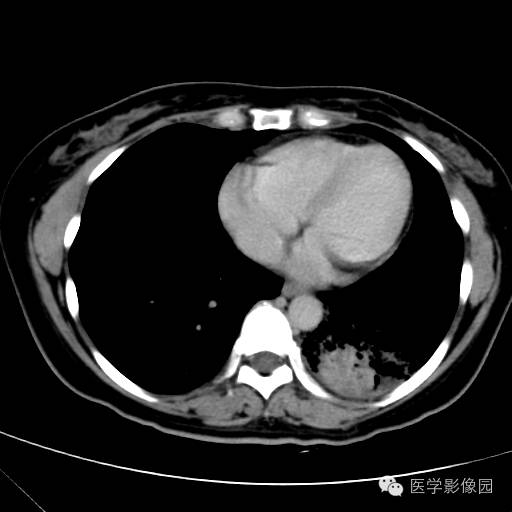

肺叶实变性支气管肺泡癌1例CT影像表现